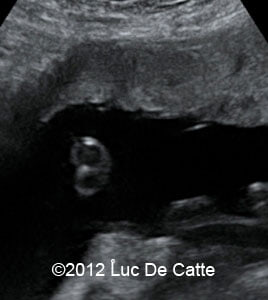

Image 3, 4: Single umbilical artery and ocular hypertelorism

screenshot_159

screenshot_158

• Ocular hypertelorism

• Single umbilical artery